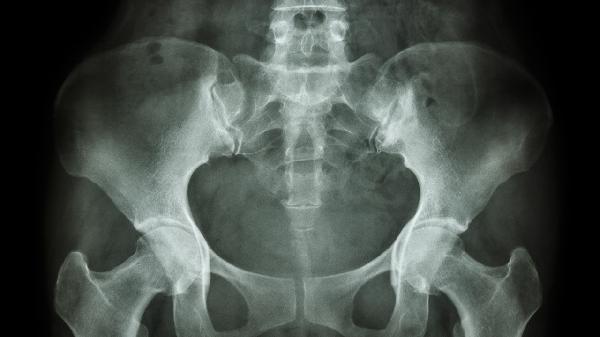

骨盆移位有什么症状

骨盆移位可能导致腰背疼痛、步态异常、下肢麻木等症状,严重时可能影响日常生活。治疗方式包括物理治疗、药物治疗和手术治疗,具体方法需根据病情严重程度选择。